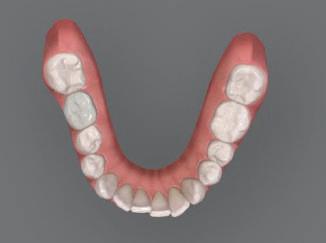

20 Dental Tribune Bulgarian Edition / октомври 2022 г. П ациентите със завършен растеж и скелетни проблеми обикновено представляват предизвикателство за ортодонт ската практика. Необходимостта от изваждане на зъби в комбинация с особеностите на възрастовата ортодонтия изисква особено внима ние. Фокусът върху критично важното значение на позицията на долните резци във връзка с дългосроч ната стабилност и постигането на оптимални оклузални взаимоотношения при затварянето на екстракционните пространства лесно може да излезе извън контрол. Когато към тези чисто кли нични проблеми се добави и стресът от натоваре ната практика, предизвикателството става още по-голямо. Всички тези фактори налагат използ ването на доказан подход с ясни и последовател ни стъпки, в което се разкрива силата на дисциплината „Алекзандър“ – предвидим протокол през целия процес на елиминиране на ротациите, ниве лиране на дъгите, затваряне на екстракционните пространства и финализиране на случая. Именно такъв е и случаят, който презентираме –екстракционен, скелетен клас 3 при възрастен па циент, лекуван по системата „Алекзандър“. ПРЕДВИДИМИ РЕЗУЛТАТИ ПРИ ПАЦИЕНТИ СЪС ЗАВЪРШЕН РАСТЕЖ И СКЕЛЕТЕН КЛАС 3, ИЗПОЛЗВАЙКИ ЕКСТРАКЦИОННО ЛЕЧЕНИЕ ПО ДИСЦИПЛИНАТА „АЛЕКЗАНДЪР“ Д-р Радой Димитров, България Преди започване на лечение клиничен случай | ортодонтия Фиг. 1а–1e Преди започване на лечение. Пациентът пристига в практиката с основното оплакване от невъзмож ност за нормално дъвчене. Снета е цялата необходима диагностична ин формация. Фиг. 1f–1h Снимки в профил и анфас. Фиг. 1i–1k Панорамна снимка, телерентгенография и анализ на телерент генография. Фиг. 1а Фиг. 1d Фиг. 1f Фиг. 1g Фиг. 1h Фиг. 1e Фиг. 1b Фиг. 1c Фиг. 1i Фиг. 1j Фиг. 1k

closed.

21Dental Tribune Bulgarian Edition / октомври 2022 г. ДИАГНОСТИЧНИ РЕЗУЛТАТИ: 1. Възраст на пациента: 21 години 2. Скелетен клас III (ANB 0) 3. Зъбен клас 3 4. Ръбцова захапка във фронта, кръстосана в дисталните участъци 5. Тясна горна челюст 6. Overjet – 0 мм, Overbite – 0 мм 7. Несъответствие на горната с долната средна линия 8. Единични контакти в ЦО 9. Хиподивергентен тип на растеж SN/MP – 33.5 10. Неравен гингивален контур 11. Неравна линия на усмивката 12. Тенденция за рецесии в долен фронт ПРЕПОРЪЧИТЕЛНО ЛЕЧЕНИЕ: Пълно ортодонтско лечение с метални брекети „Алекзандър“ Корекция на клас 3 захапката в областта на кучешките зъби с екстракция на първите пре молари в долна челюст Корекция на кръстосаната захапка в дистални участъци Коригиране на ръбцовата захапка във фронта Подобряване на ОJ и OB на пациента Стрипинг в долен фронт Подреждане на зъбите в горната и долната челюст Професионално хигиенизиране и профилактични дентални прегледи са препоръчителни на всеки 6 месеца. 1-ви месец След 1 месец са залепени брекети в горната челюст – поставена е еластична дъга. 016 NiTi. В долната челюст са елиминирани ротациите, поставена е стоманена дъга. 016SS, закалена с ток, и еластична верижка за затваряне на пространствата. 3-ти месец В долната челюст е поставена трета дъга – 17 x 25 NiTi с къси лигатури и верижка

В горната челюст се затварят пространствата с дъга .016SS и верижка. 5-и месец На 5-ия месец след залепяне на брекетите в долната челюст е поставена стоманена дъга 16 x 22 SS с четвъртито сечение, омега луп и тай бек. В горната челюст е поставена дъга 17 x 25 NiTi. Поради липсата на стабилни оклузални контакти са поставени лингвални верижки в областта на моларите, за да се предотврати нежелана ротация на 7-ите зъби. 6-и месец На 6-ия месец от началото на лечението са екстрахирани долните първи премолари, поставена е дъга 16 x 22 SS със затваряща чупка teardrop. Чупката се активира всеки месец по 1 мм с чинч-бек. клиничен случай | ортодонтия СТЪПКИ НА ЛЕЧЕНИЕТО Начало на лечението Лечението започва с поставяне на апарат за бърза експанзия в горната челюст. През първия месец от лечението са направени 24 оборота на апарата за експанзия. Залепени са брекети в долната челюст, поставена е дъга 17x25 CuNiTi, като са предпи сани клас 3 ластици (1/4”,4 1/2 oz) по време на сън, за да се осигури контрол върху торка на долните резци. Фиг. 2а Фиг. 3a Фиг. 4a Фиг. 3b Фиг. 4b Фиг. 3c Фиг. 4c Фиг. 3d Фиг. 4d Фиг. 3e Фиг. 4e Фиг. 5a Фиг. 5b Фиг. 5c Фиг. 5d Фиг. 5e Фиг. 6a Фиг. 6b Фиг. 6c Фиг. 6d Фиг. 6e Фиг. 7a Фиг. 7b Фиг. 7c Фиг. 7d Фиг. 7e Фиг. 2b Фиг. 2c Фиг. 2d

Dental Tribune Bulgarian Edition / октомври 2022 г.22 клиничен случай | ортодонтия 14-и месец В горната и долната челюст са поставени последни стоманени дъга с омега луп и тай бек – 17 x 25 SS с четвъртито сечение. Назначени е ластик за средната линия в комбинация с клас 3 ластик (1/4”, 6 1/2 oz). Контролни рентгенографии 13-и месец Екстракционните пространства са затворени. Направена е контролна панорамна снимка за оценка позицията на корените. Взето е решение за презалепване на брекетите на 12, 22 и пръстените на 36 и 46. 21-ви месец Средната линия в горната и долната челюст съвпадат. Ластиците са спрени. Свалени са пръстените и брекетите в горната и долната челюст, зигзаг ластици не са използвани поради благоприятните оклузални взаимоотношения. Фиг. 11j Ортопантомография в края на лечението. Фиг. 11k Телерентгенография след края на лечението. Фиг. 11l Анализ на телерентгенографията след лечението. Фиг. 11m Последователност на дъгите в горната и долната челюст Фиг. 11n Суперимпозиция на PreOp и PostOp ортопантомографии. 10-и месец Затварянето на пространствата е предвидимо и контролирано, без да се отварят пространства в зъбната дъга. Фиг. 8a Фиг. 8b Фиг. 8c Фиг. 8d Фиг. 8e Фиг. 10a Фиг. 10b Фиг. 10c Фиг. 10d Фиг. 10e Фиг. 9a Фиг. 9b Фиг. 9c Фиг. 9d Фиг. 9e Фиг. 9f Фиг. 11a Фиг. 11f Фиг. 11j Фиг. 11l Фиг. 11m Фиг. 11n Фиг. 11k Фиг. 11g Фиг. 11h Фиг. 11i Фиг. 11b Фиг. 11c Фиг. 11d Фиг. 11e

Dental Tribune Bulgarian Edition / октомври 2022 г. 23клиничен случай | ортодонтия реклама Лечението е продължило 21 месеца. Проведено е домашно избелване с индивидуални шини. За автора: Д-р Радой Димитров завършва с отличие Факултета по дентална медицина към МУ–София през 2015 г. В продължение на 5 години работи в няколко водещи практики в София, като през 2019 г. заедно със своята съпру га д-р Траяна Димитрова основават собствена практика в гр. Гоце Делчев –Dimitrovi Dental Care. Посещава редица курсове за повишаване на квалификаци ята, но най-сериозен тласък в развитието на ортодонтската си практика получава след завършването на комплексната ортодонтска програма, воде на от д-р Иван Горялов, базирана на дисциплината „Алекзандър“ – система с повече от 50 години опит в целия свят. Д-р Димитров е член на Българския изследователски клуб „Алекзандър“. Взе ма участие като гост-лектор в симпозиума с международно участие The Power of the Alexander Discipline, който се проведе на 14–15.05.2022 г. С д-р Ди митров можете да свържете на тел. +359885 252 025. Заключение Представеният случай е ярък пример за възможностите и красо тата на дисциплината „Алекзандър“ – приложен е утвърден под ход с ясни правила и са постигнати очакваните цели. Резулта тът ще бъде дългосрочно стабилен, тъй като са спазени всички правила, които се отнасят към максимално комфортната пози ция на зъбите в края на лечението. Постигнати са красива усмив ка и стабилна оклузия. ПОСТИГНАТИ РЕЗУЛТАТИ ОТ ЛЕЧЕНИЕТО 1. Коригирана ръбцова захапка 2. Коригирана клас 3 захапка в областта на ку чешките зъби 3. Коригирана кръстосана захапка в дисталните участъци 4. Коригиран овърджет и овърбайт 5. Разширена е горната зъбна дъга 6. Подредени зъби в горната и долната челюст 7. Постигната е стабилна захапка с множество контакти в ЦО 8. Драматично е подобрена дъвкателната функ ция 9. Подобрена е линията на усмивката ДРУГИ ПРОВЕДЕНИ ДЕНТАЛНИ ПРОЦЕДУРИ 1. Домашно избелване на зъбите 2. Екстракция на мъдреците Фиг. 12a Фиг. 12b Фиг. 12c Фиг. 12eФиг. 12d Фиг. 12f Фиг. 12g Информация за дати, цени и отстъпки www.bracescourses.com 0889 22 55 01 Практически курсове лектор д-р Иван Горялов Дисциплината „Алекзандър“ ПЪТЯТ КЪМ СУПЕРУСМИВКИТЕ 100% връщане на цялата сума, ако не сте удовлетворени след преминаване на Ниво 1 Директно и индиректно залепяне на брекети Анализ, диагноза и план на лечение Лечение на клас 2 дълбока захапка Екстракционно лечение Лечение на клас 3 отворена захапка НИВО 5НИВО 1 НИВО 2 НИВО 3 НИВО 4